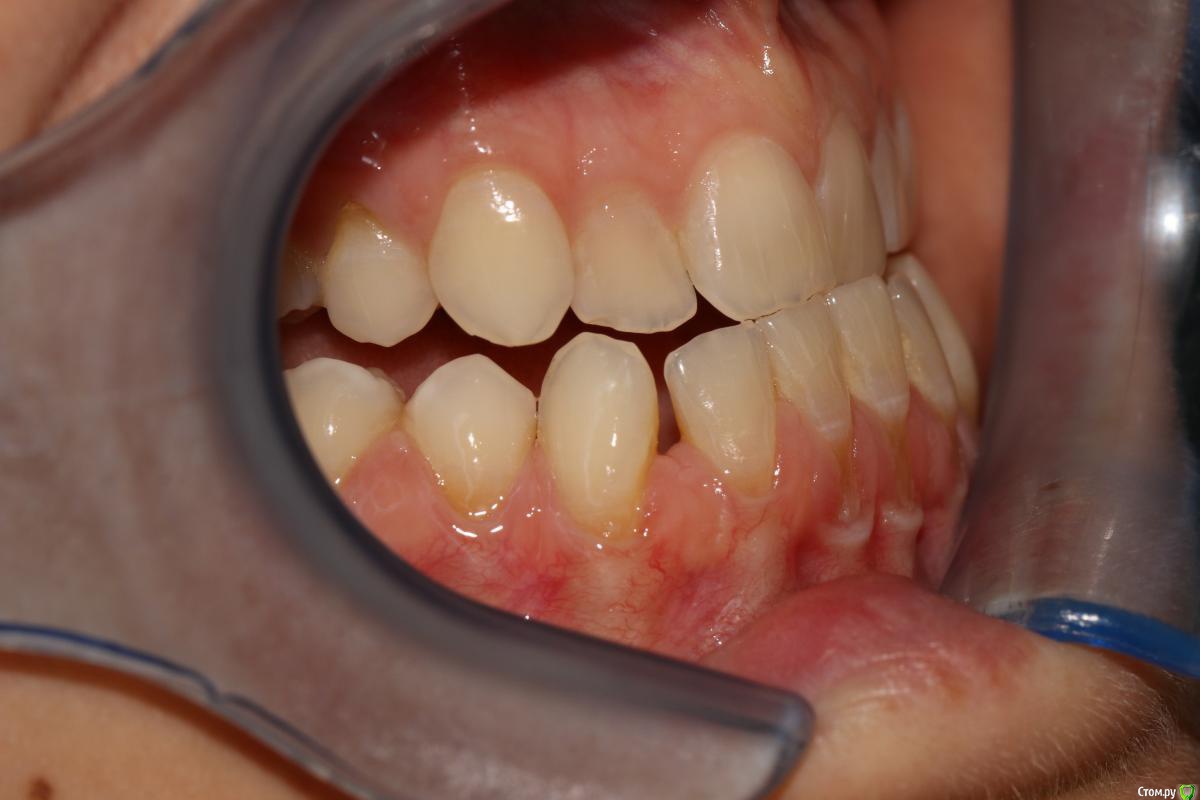

rytovst Опубликовано 15 сентября, 2018 Поделиться Опубликовано 15 сентября, 2018 Здравствуйте ,коллеги!Посоветуйте ,как и чем лучше закрыть данные рецессии перед ортодонтическим лечением.Склоняюсь к расщепленному лоскуту и ССТ с неба + коронально-смещенный лоскут . Может быть взять ССТ с эпителиальной полоской? Ссылка на комментарий

rytovst Опубликовано 16 сентября, 2018 Автор Поделиться Опубликовано 16 сентября, 2018 -фото ,как вы видите ,не в прикусе ( 6 зубы не смыкаются) -дистальная дизокклюзия - произвести протрузию на нч Ссылка на комментарий

Irouil Опубликовано 16 сентября, 2018 Поделиться Опубликовано 16 сентября, 2018 зачем тогда спрашивать, если сделаете, как нравится?Скейлинг + ЭДТАМожет коллега с Вас пример берет: уже все сделал, а спрашивает из спортивного интереса?) Я бы тоже в резцах шел с эпителием и туннель, в клыках/премолярах может полностью деэпителизировать (если не одним трансплантатом брать будете). В этом случае, имхо, показания к пародонтологии даже без ортодонтии Ссылка на комментарий

Дмитрий Л. Опубликовано 16 сентября, 2018 Поделиться Опубликовано 16 сентября, 2018 В этом случае, имхо, показания к пародонтологии даже без ортодонтии Я не об этом. Если резцы планируется сдвинуть дистально, то рецессия может уменьшится уже уже от этого, соответственно и успех хирургии будет выше после ортодонтии, а не до. - произвести протрузию на нч Вот честно я не понял здесь вас( Вообще здесь не рецессия, а пародонтит. И устранить нужно причину. Уздечка, преддверие...?+1 за туннель и не уверен по поводу коронарного смещения лоскута: риск порвать лоскут + натяжение от губы только увеличится. Ссылка на комментарий